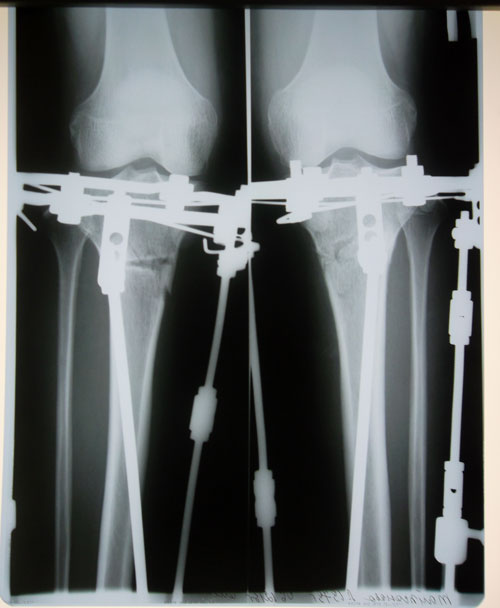

рентген в 2 месяца.

Здравствуйте, Лейла! По результатам рентгена, планируйте снятие аппаратов с 5, 6 января 2014г.. На обратную дорогу возьмите костыли!